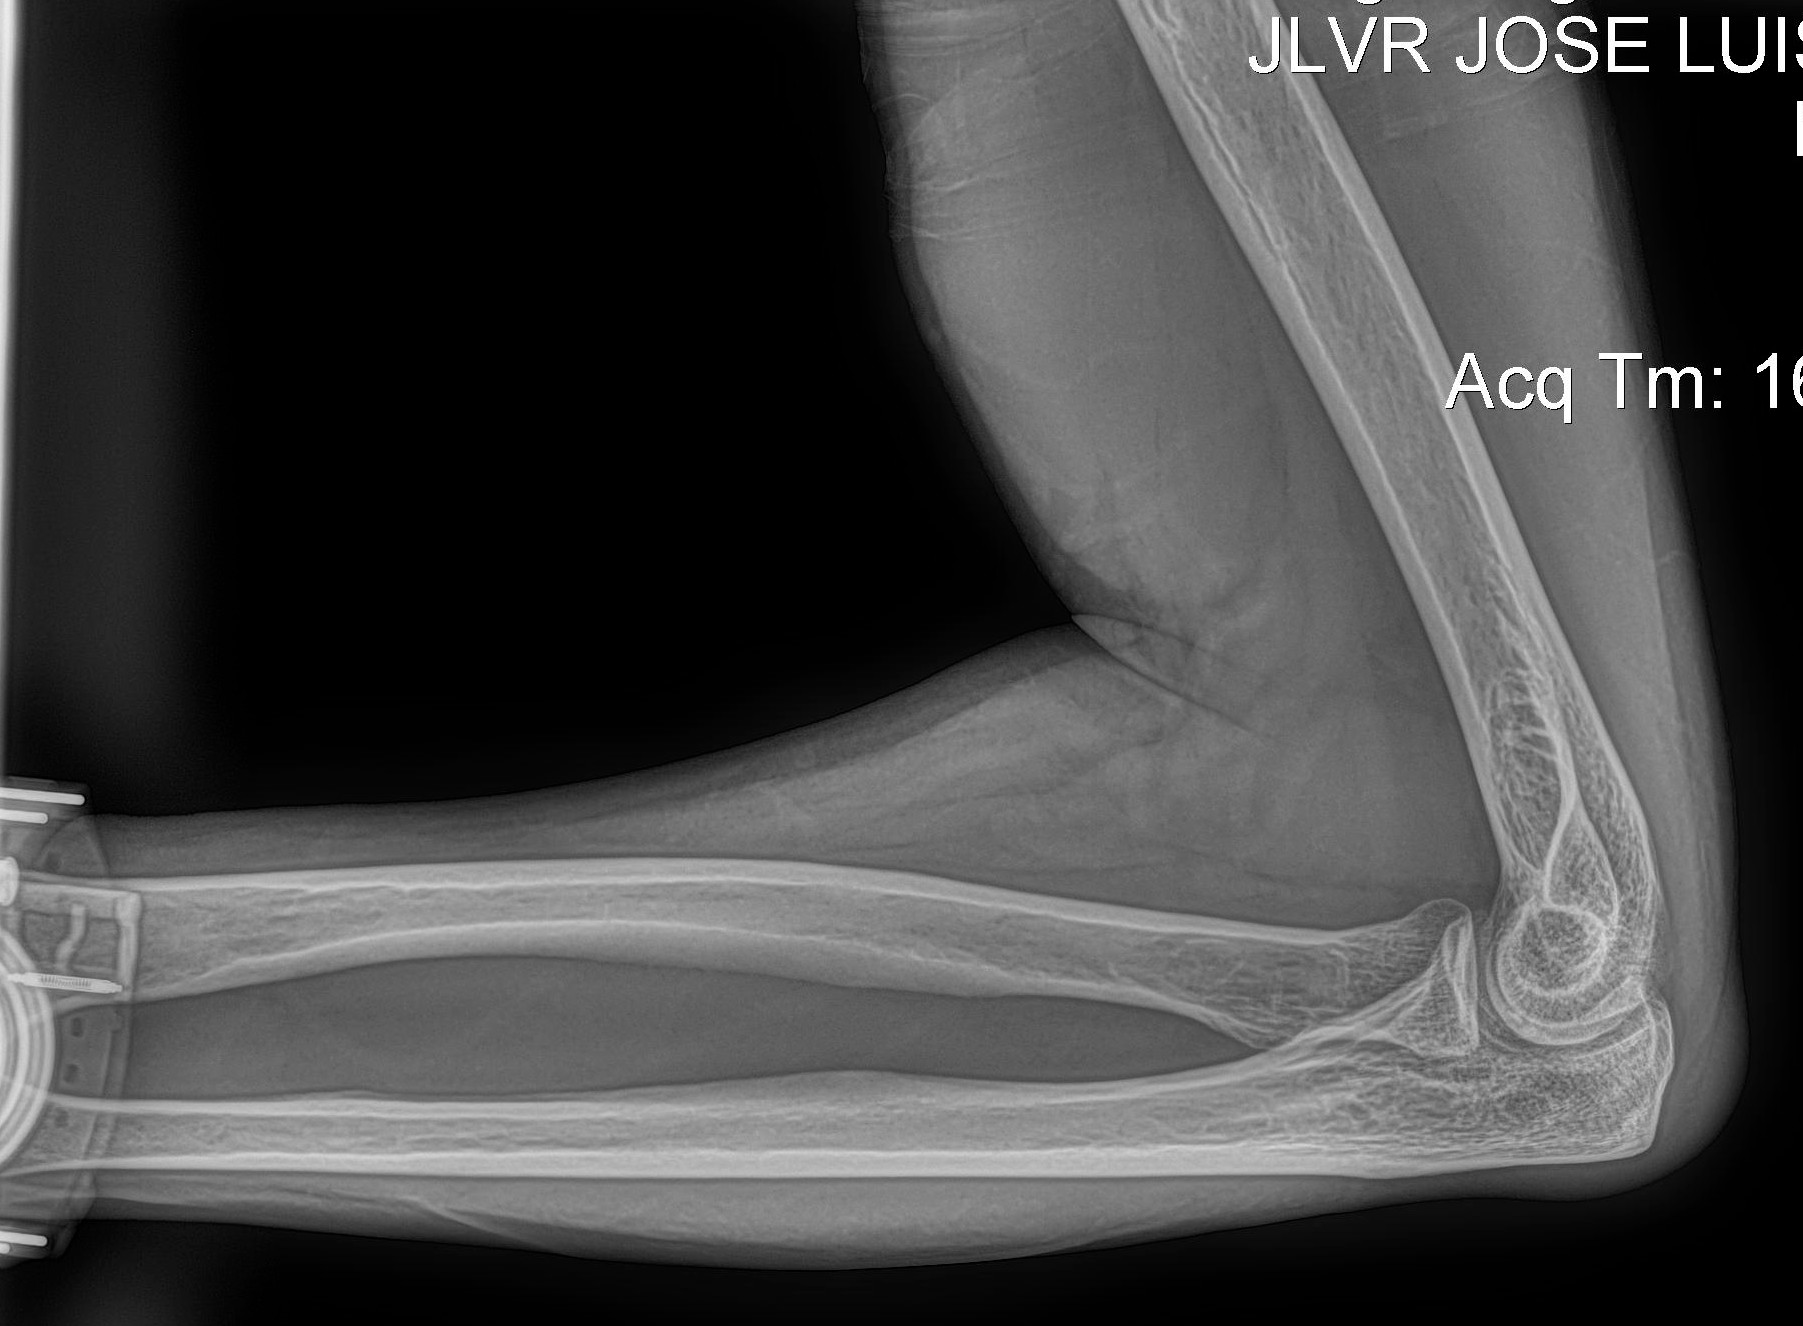

Radiología Digital como Herramienta Complementaria en el Dictamen de Bienes Muebles

Desde el descubrimiento de los rayos “X” y las placas radiográficas por Wilhelm Conrad Roentgen y su posterior difusión a través de la Asociación Físico médica de Wurzburg el 28 de diciembre de 1895, que fue la primera asociación que habló de los nuevos rayos que podían penetrar el cuerpo y fotografiar los huesos, ha habido muchos cambios tanto en la forma de obtener, procesar e incluso en la forma de visualizar, manejar y almacenar las placas radiográficas.